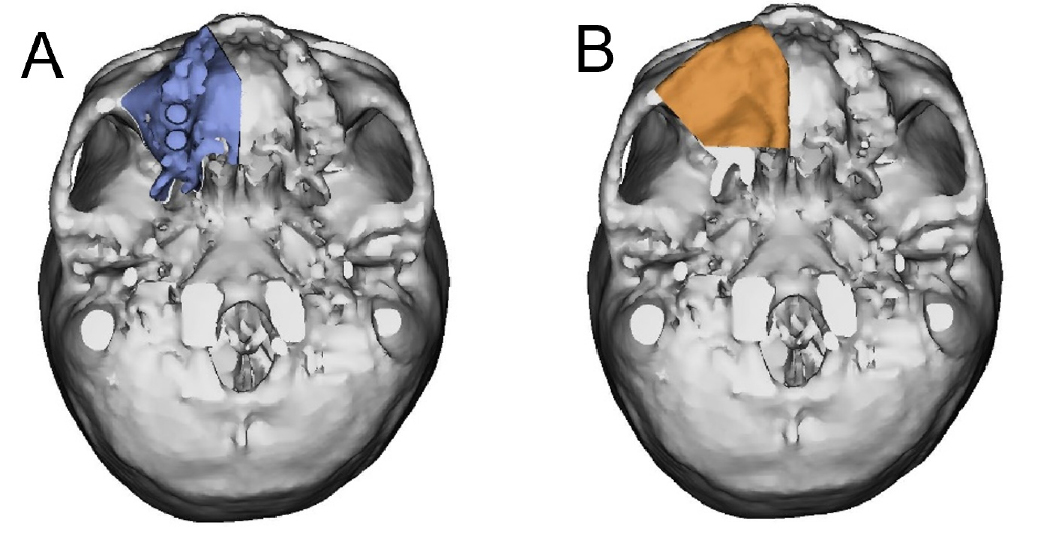

Before the reconstruction with the scapular free flap, virtual surgical planning (VSP) was performed using Mimics (version 16.0; Materialise Dental NV, Leuven, Belgium) and Simplant Pro 14.0 software program (Materialise Dental NV). The patients’ preoperative head and upper extremity CT scans were segmented, and the resulting three-dimensional models of the maxilla and scapula were loaded into the Mimics software for VSP. A partial maxillectomy was performed virtually, and the scapular model was positioned to replace the defect (Fig. 3). The height and width of the lateral border of the scapula were sufficient for the implant placement. Therefore, reconstruction of the lateral border of the scapula on the alveolar side was planned.